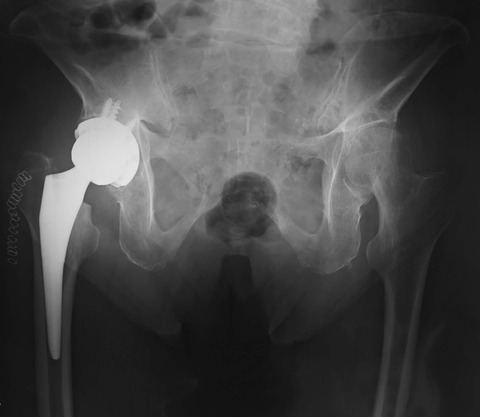

この画像では、骨盤が極端に後傾しているものの、カップの前方開角は20度ぐらいにみえます。私は臥位よりも立位の状態の方をより重視しています。

このため、カップの前方開角は、どちらかと言えば立位に合わせにいきます。仮にこの患者さんに対して臥位に合わせてカップを設置すると立位時に前方脱臼するリスクが高まります。